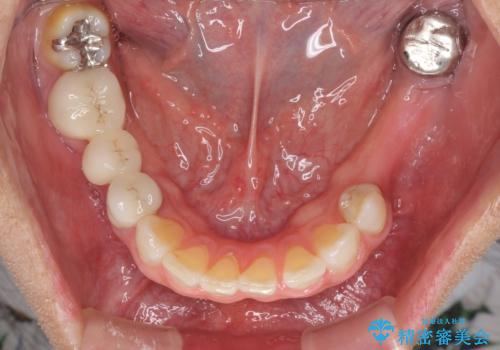

- 口の中に気になるところが沢山あるものの、地元ではなかなか治療を行ってくれるところがないとのことで、沖縄県の離島より来院された患者様です。

金属を使用した前歯のブリッジや奥歯の銀歯は全てオールセラミッククラウンまたはセラミックインレーとし、左下の奥歯はインプラントにより治療を行うこととしました。

外科処置を行うため、治癒を待つ期間が数ヶ月あるため、その期間を利用して下顎前歯のスペースを矯正治療で閉じることとしました。